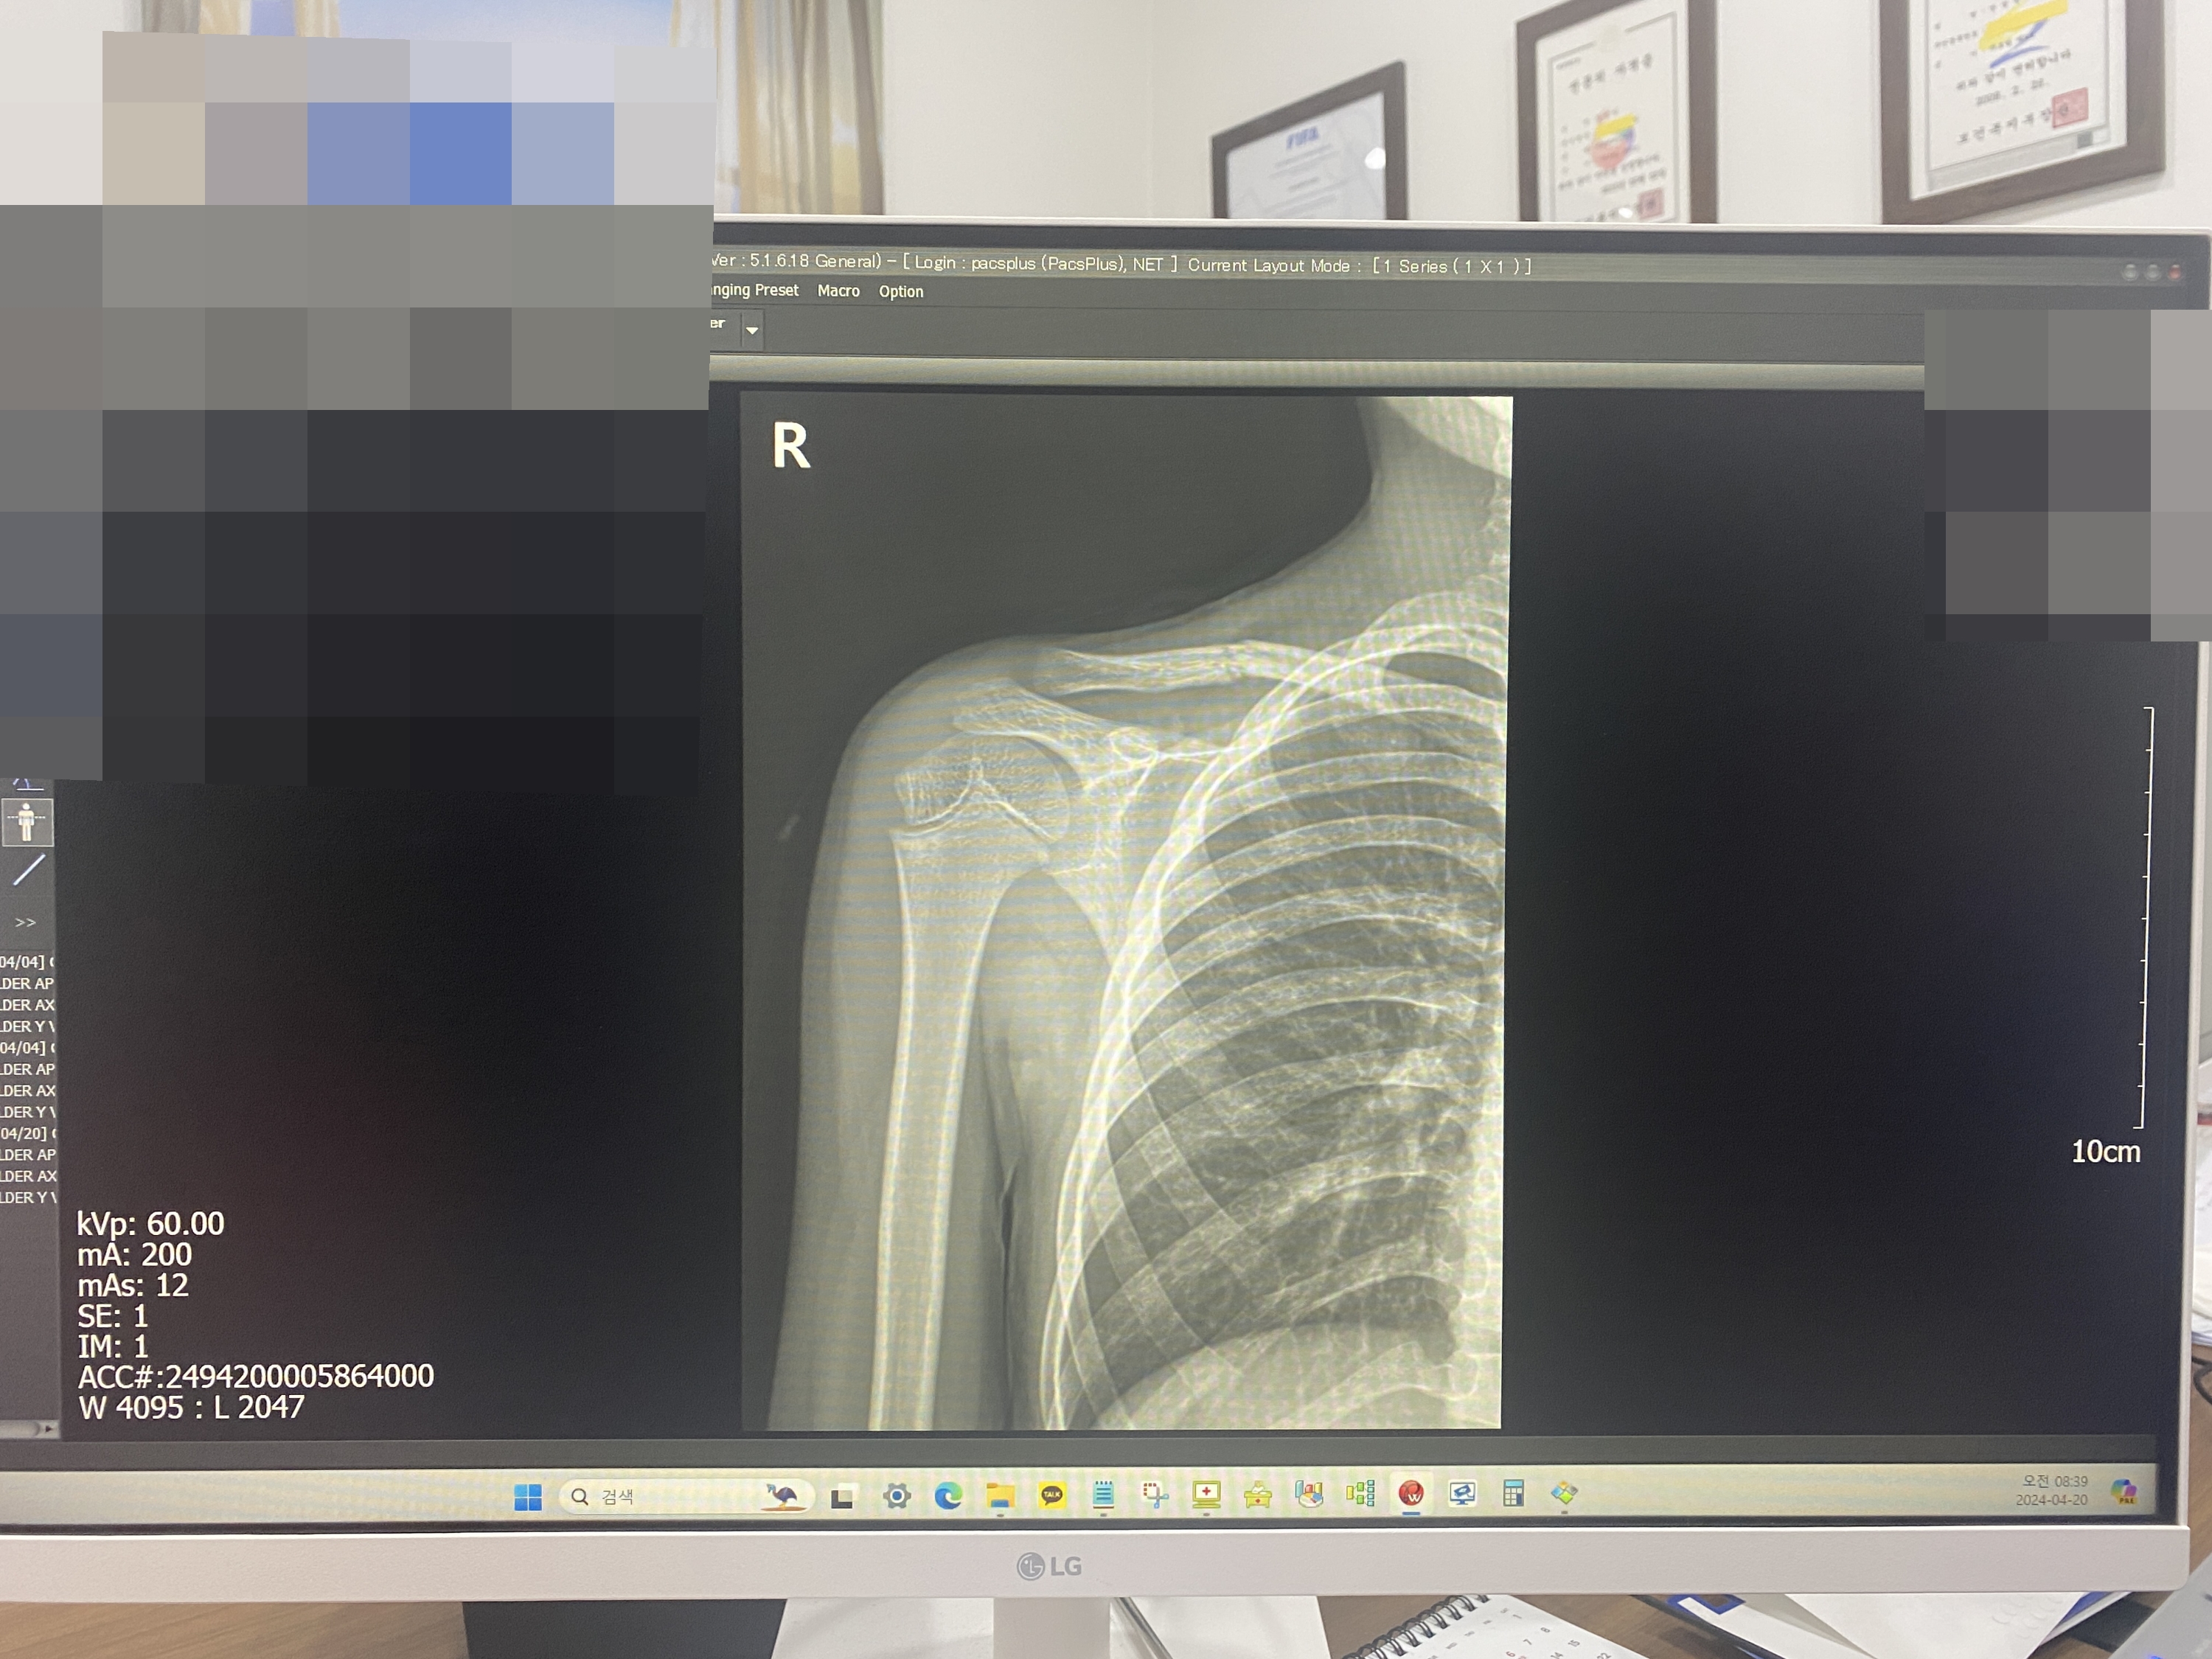

왼쪽이 부러진 쇄골 오른쪽이 정상 쇄골의 뼈모양이에요.

사진보면 완전히 어긋나있는데 부러졌을때 아이가 얼마나 아팠을까요ㅜㅜ

쇄골 부러지고 두달 지난 사진이에요.

부러진날 보면 뼈가 심하게 어긋나 있었는데 많이 내려온게 보이시죠? 저게 다 붙은거래요~